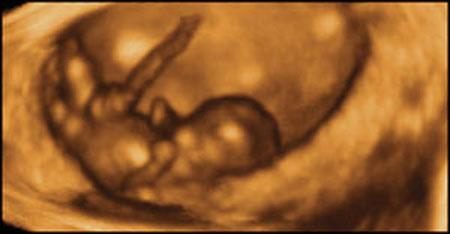

Ультразвуковые съёмки аборта на 12 неделе явно показывают: ребёнок чувствует боль, как любой из нас, и прекрасно понимает, что его хотят убить - он всеми силами старается отодвинуть от себя инструмент и широко раскрывает рот в безмолвном крике, когда у него отрывают сначала ноги, затем часть туловища…

Голову извлекают в последнюю очередь и лицо убитого ребёнка всегда искажено гримасой боли и ужаса. По этим кадрам видно, что практически нет разницы, убить ли 3-месячного ребёнка в утробе или отрезать руки -ноги -голову 5-летнему малышу. Без анестезии и в полном сознании.

- Фильм американского врача Бернарда Нэйтансона, названный «Безмолвный крик», показал всему миру, что такое аборт на сроке 11 недель беременности. Многие врачи и медсестры, посмотрев фильм, прекратили участвовать в абортах.

Это документальный фильм, и авторы рекомендуют соблюдать осторожность при его показе, поскольку некоторые кадры могут вызвать у человека психологический шок: безмолвный крик внутриутробного младенца, искаженное от боли лицо ребенка, погибающего на наших глазах...

Из закадрового текста к фильму: «Инструмент еще не коснулся ребенка, но он уже возбужден, его сердечные удары учащаются и достигают приблизительно 200 ударов в минуту. Вакуум-кюретка нащупывает ребенка, и он широко раскрывает рот в безмолвном крике».